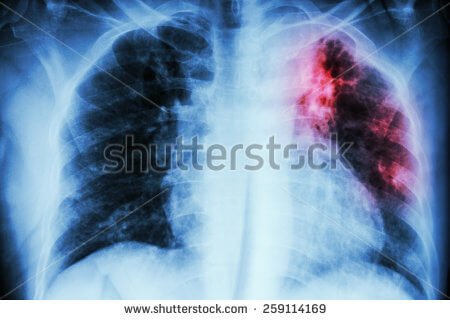

Tüberküloz tanısı, balgamda verem mikrobunun gösterilmesi ile konulur. Hastanın yakınmaları ve akciğer film bulguları ile hastalıktan şüphelenilir.